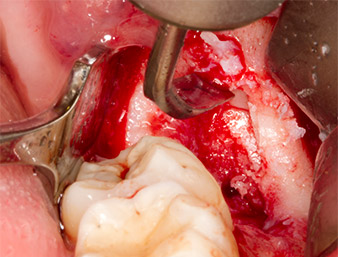

After block and local anaesthesia, the operating site was opened up and the soft tissue exposed for buccal retromolar access (Fig. 3).

sulcular incision

Fig. 3: The sulcular incision begins in mid-tooth 36 (LL6), with distal extension on the ascending ramus.

The tissue above the root remnant was not completely ossified and consisted for the most part of granulation tissue modified by inflammation (Fig.4).

Granulation tissue

Fig. 4: Two Langenbeck retractors and a raspatorium expose the operating area. Granulation tissue of the incompletely healed first osteotomy can be seen.